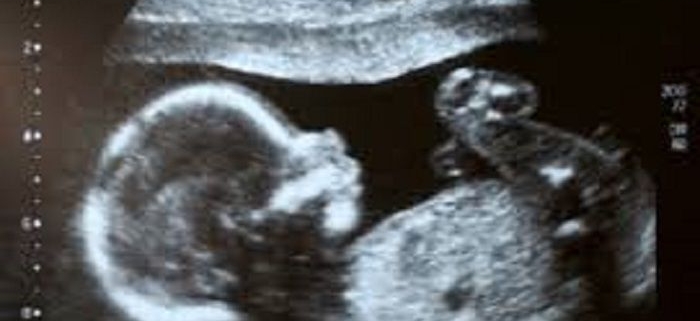

- سونوگرافیNT (nuchal translucency)استاندارد

زمان انجام غربالگری سه ماهه اول، شروع هفته 11 تا 13 هفته + 6 روز بارداری است.